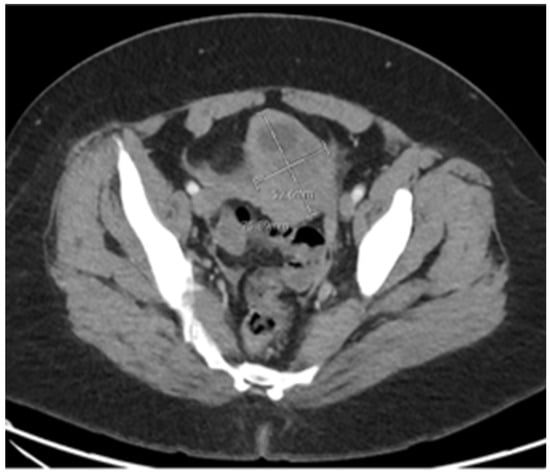

Case Summary